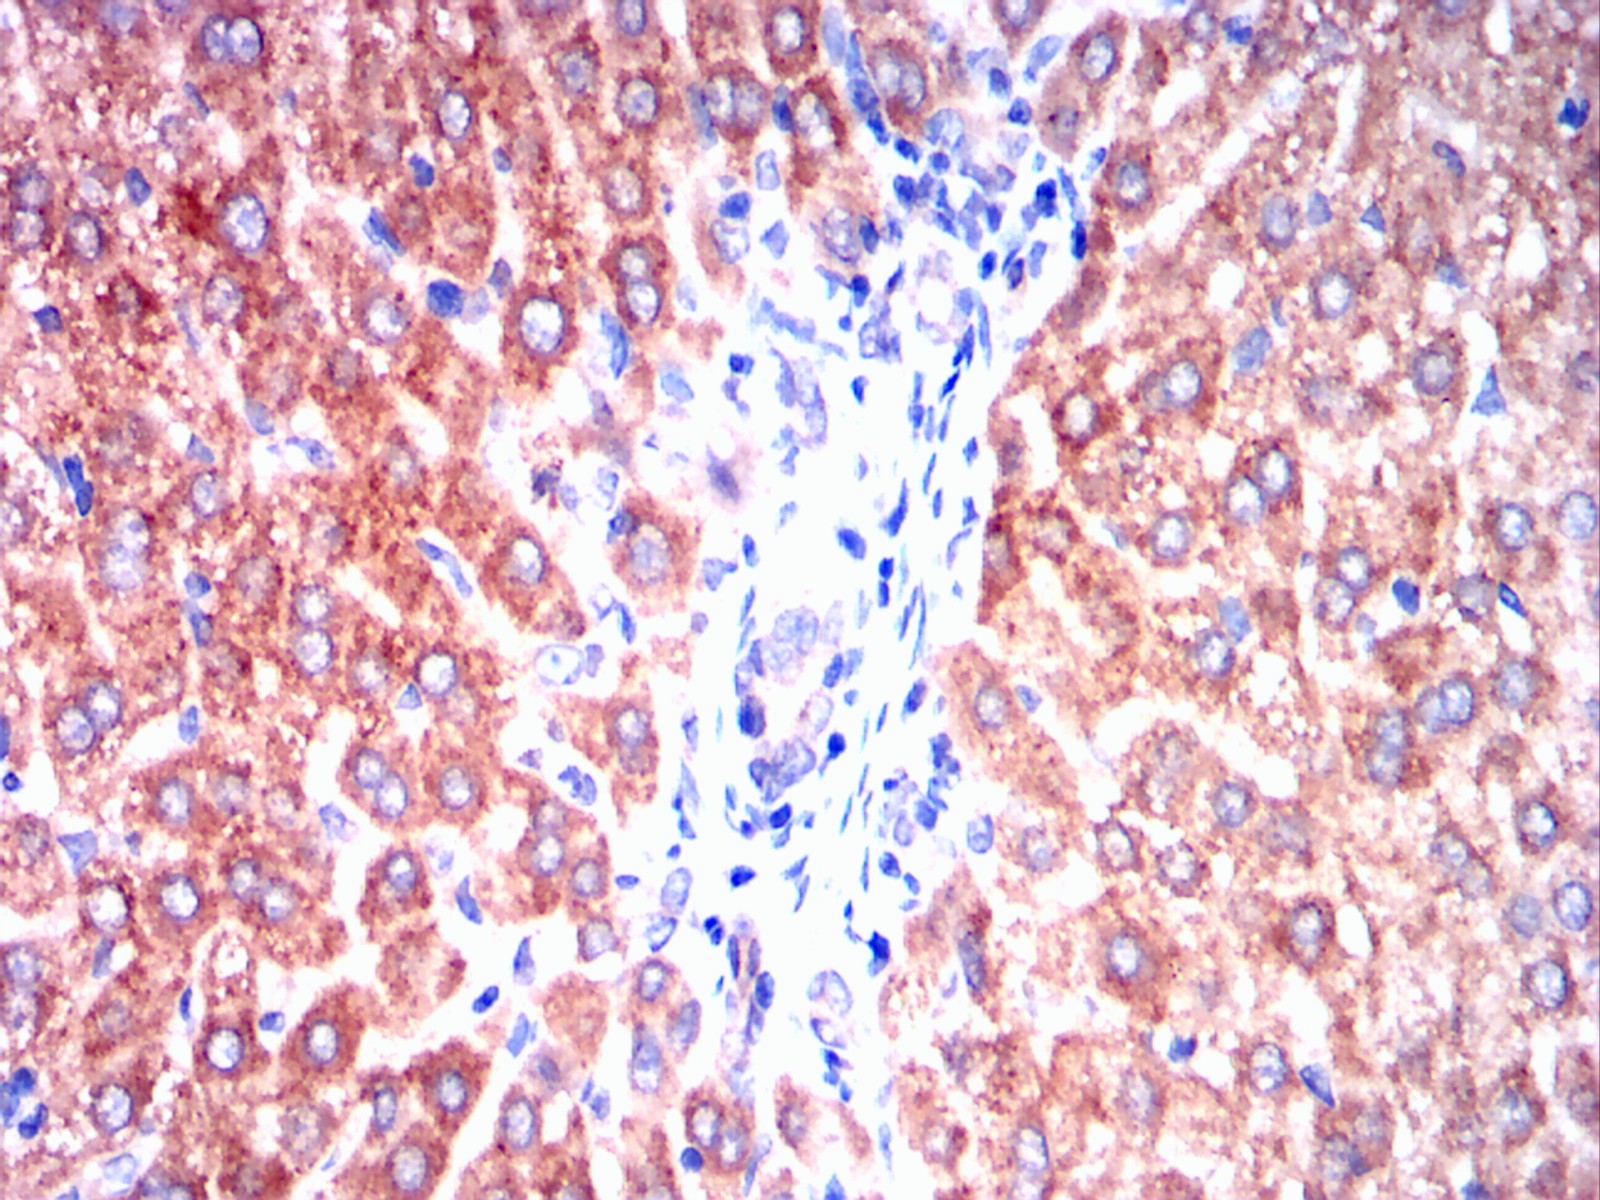

Immunohistochemical analysis of paraffin-embedded rabbit liver tissues using ERBB3 mouse mAb with DAB staining.